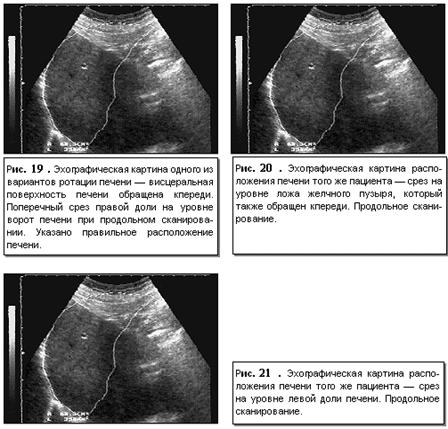

органов пищеварительной системы. Ротация печени – изменение ее расположения

вдоль одной из осей – длинной или короткой. Чаще наблюдается вариант ротации по

длинной оси, при котором к передней брюшной стенке обращен не нижний край

печени, а либо висцеральная, либо диафрагмальная поверхности (рис. 19-21).